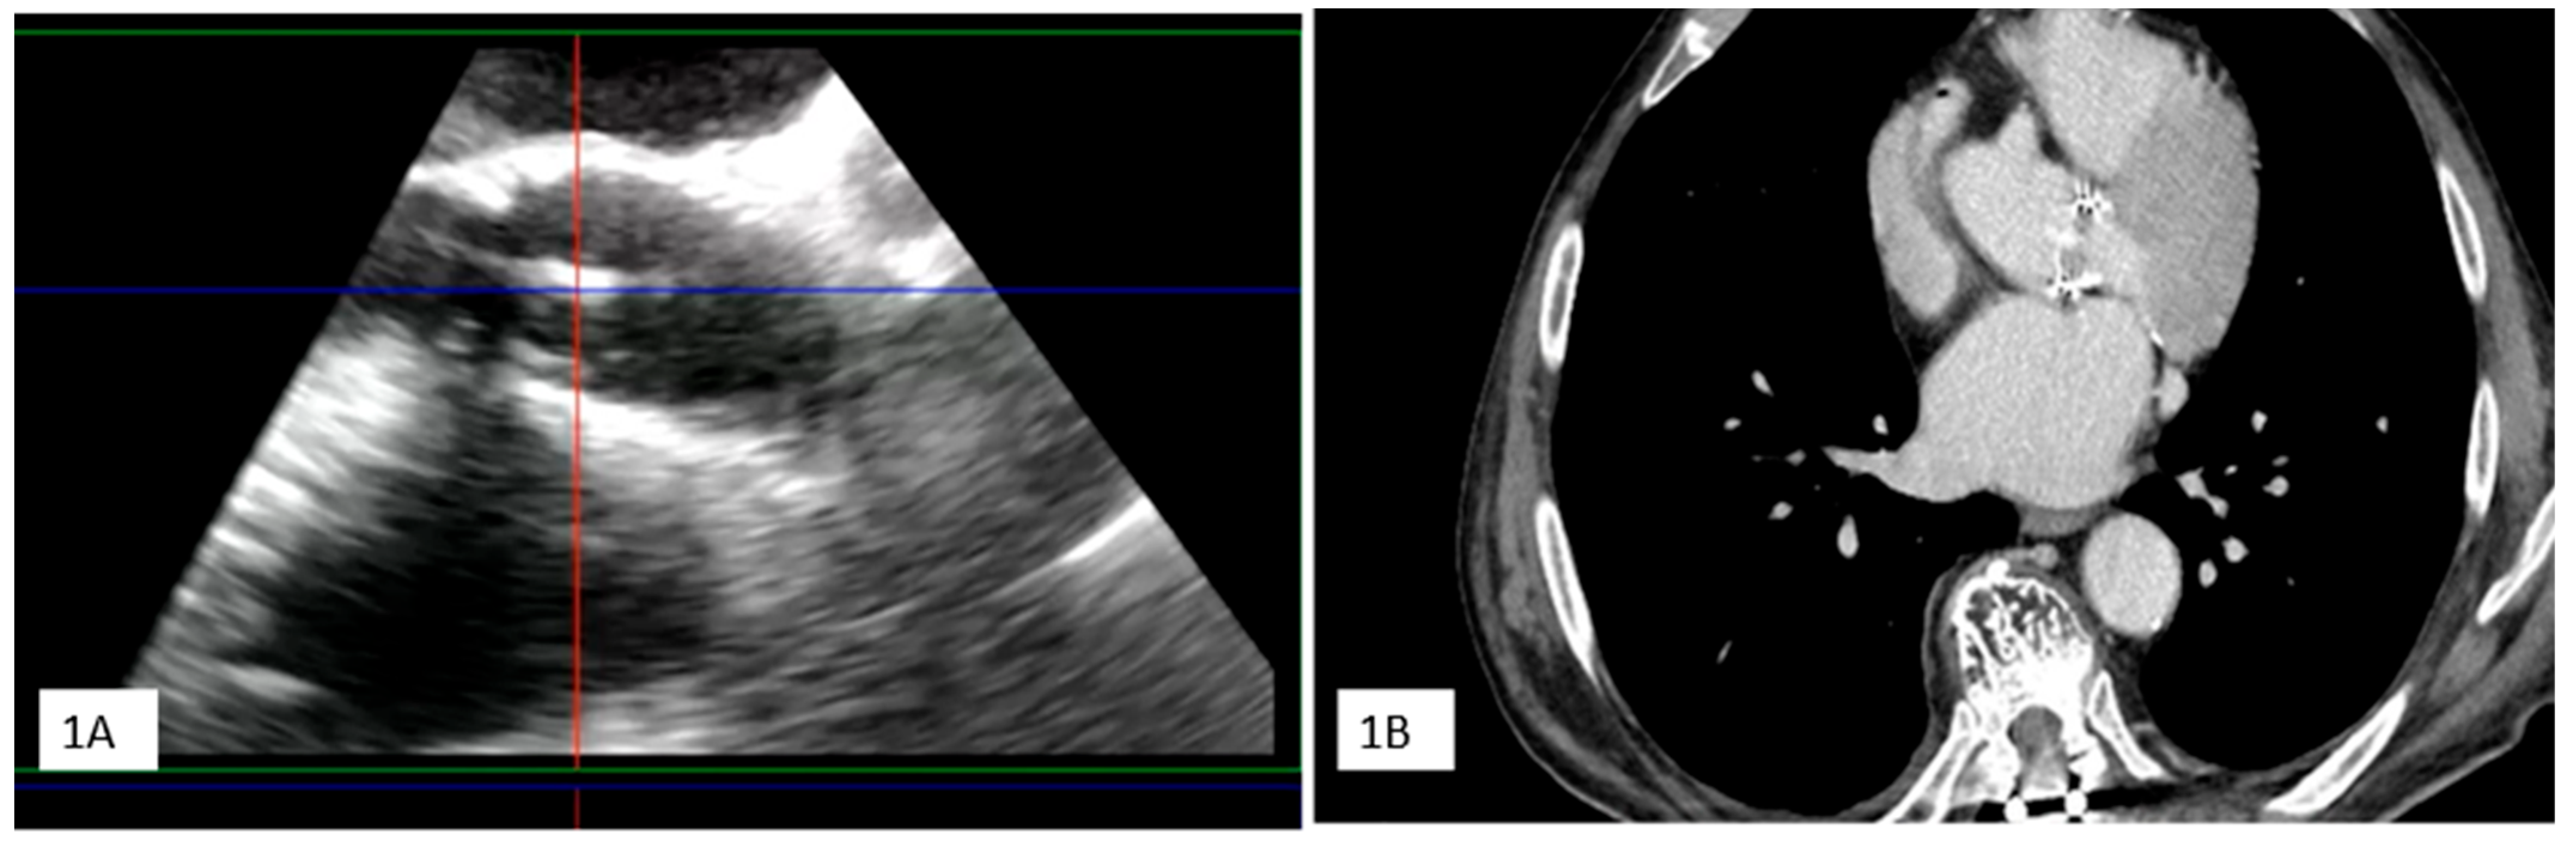

| Clinical Case 2. Unexpected endocarditis at opprtunistic echocardiography follow-up. A 60-year-old woman was observed at our heart valve clinic for a scheduled 3-month survey following surgical mitral valve repair of prolapse-related mitral regurgitation. The patient was asymptomatic under medical therapy, including a beta-blocking agent and routine early anticoagulation with dicumarol. Clinical examination was normal. Transthoracic echocardiography showed a small iso-echogenic mass on the atrial side of the posterior mitral leaflet. The subsequent transesophageal echocardiography (1 = 2D-TEE, 2 = 3D-TEE), showed a large iso-echogenic mass with an annular infiltrative appearance suggesting active valve vegetation. Blood cultures and phlogistic indices were normal. A PET examination (3 = PET) showed moderate mitral ring uptake, coherent with the recent surgical procedure. Due to the unexpected findings suggesting IE without clinical and microbiological associated criteria, TEE was re-evaluated following seven-day treatment with iv Heparin and empirical antibiotic therapy (Vancomicin, Gentamicin, Rifampicin). Owing to the persistence of mitral valve mass at high embolic risk, the patient underwent surgery. Surgical inspection (4 = surgical specimen) and histological examination confirmed IE diagnosis with a microbiological tissue culture for Enterobacter Cloacae. Following mitral valve replacement the clinical course was favorable with 1-month focused antibiotic therapy, without IE recurrence at long-term follow-up. This case underscores the importance of a careful and systematic survey following cardiac surgery to exclude silent unexpected endocarditis, especially during the first year after heart valve surgery.  |